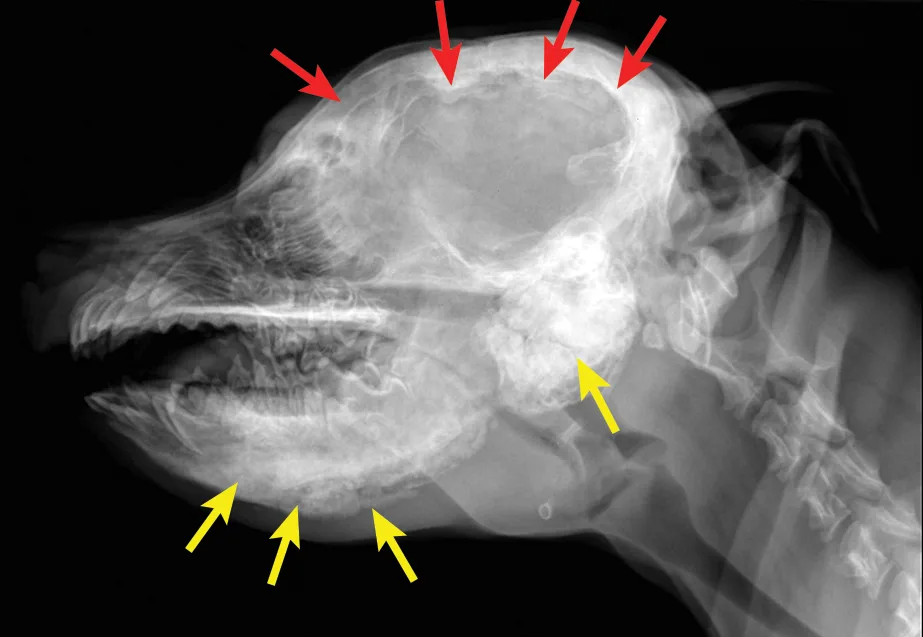

Diagnosis is based on signalment, history, clinical signs, and radiographic findings. Although biopsy and histopathology can help confirm diagnosis, they are typically not necessary, as radiographic findings are often pathognomonic (Figure 1). However, although standard radiographs can confirm diagnosis, CT may be helpful in assessing if the temporomandibular joints are affected.

(A) Lateral and (B) ventrodorsal radiographs of the skull. This patient was diagnosed with calvarial hyperostosis. Note that the frontal, parietal, and occipital bones, including the tentorium osseum, are smooth but have increased thickness and opacity (red arrows). Note the markedly irregular periosteal reactions on the mandibles and bullae (yellow arrows). This patient was unable to open its mouth much beyond what is evident on the lateral image. Images courtesy of Justin Goggin, DVM, DACVR